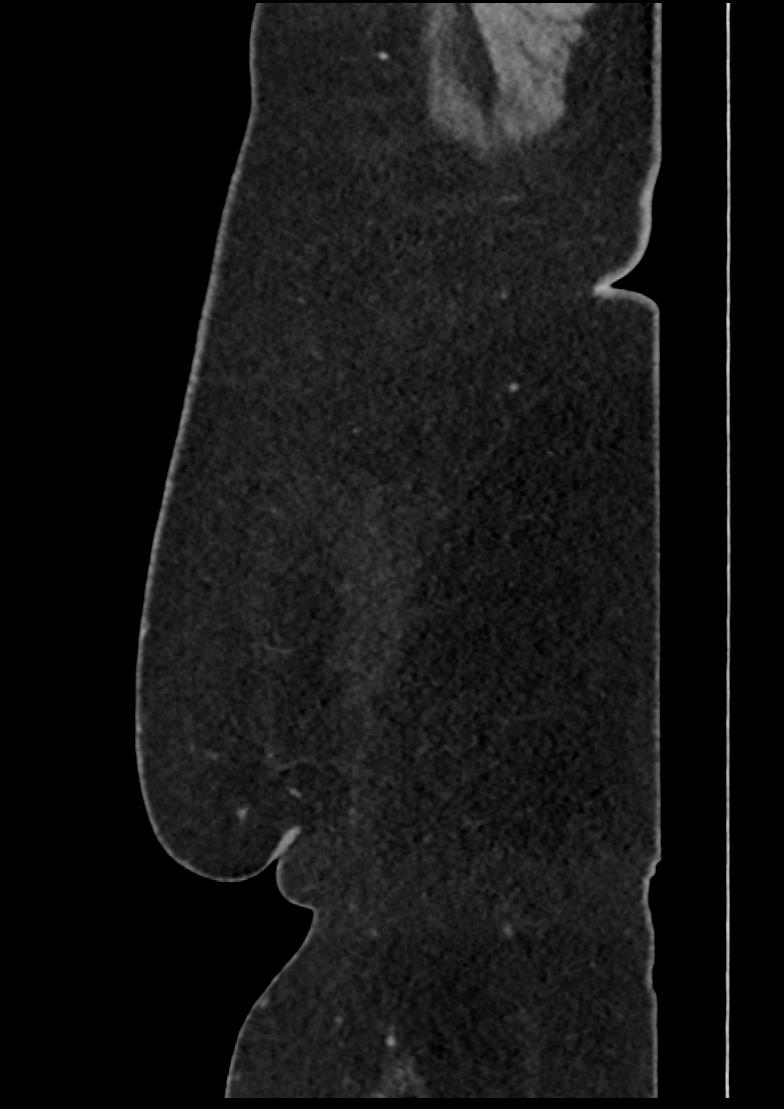

Patient: Padmakumar A. , *1988-04-24, PID: 3000069741773230809

Study Description: CT ABDOMEN

Image Series: Abdomen Sag 3mm [4]

<< Previous | Image 19 of 158 | Next >>